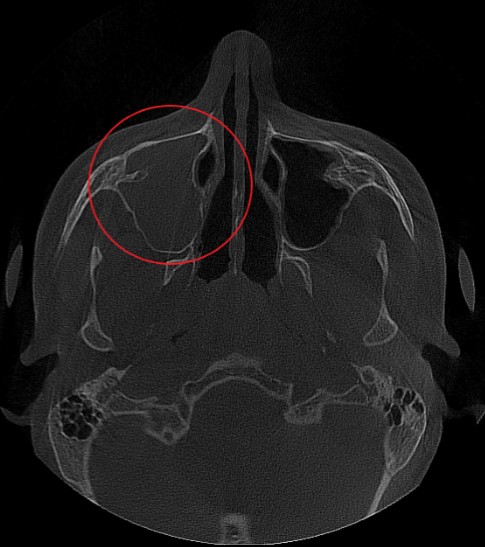

Проведена компьютерная томография околоносовых пазух, которая подтвердила наличие правостороннего гемисинусита (воспаление нескольких пазух с одной стороны), как следствие периодонтита зуба 1.6.

Представлено КЛКТ околоносовых пазух до начала лечения. Выделена зона воспаления пазух.